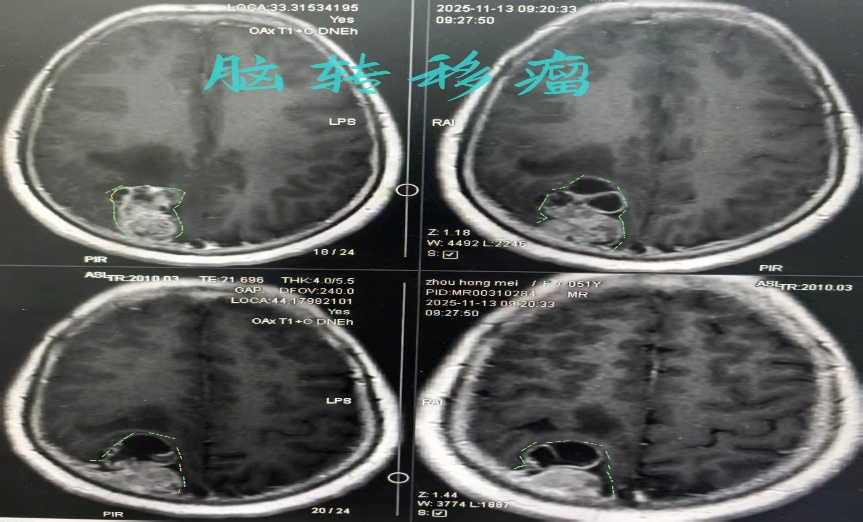

术前MRI增强影像:

针对患者急危重病情,结合既往病史、影像学检查等资料,科室紧急讨论初步诊断为肺癌脑转移瘤卒中,但也不排除属于胶质瘤或淋巴瘤导致出血可能,具体性质需病理诊断明确;另外肿瘤体积大、增强明显,位于大脑静脉血管矢状窦旁、右侧顶枕叶深部,肿瘤供血丰富,切除过程中可能出血较多,同时合并扣带回下脑疝病情,病情严重已然危及患者生命,不容犹豫。鉴于患者危重的病情,我们一方面紧急与急诊科沟通,120将患者紧急安全及时转诊东风路院本部;另一方面与手术室紧急协调,第一时间腾出急诊手术室,为救治患者提供强有力保证。在转诊过程中,神经外科值班医生将上述病情与患者家属充分沟通并签字确认,同时完善备血备皮、用药等各项准备工作,患者转诊本部过程中一路通畅,紧急转入手术室行显微镜下肿瘤切除、血肿清除手术。手术历时3小时,顺利全切肿瘤并完全清除血肿,术后患者意识清醒,除左侧肢体运动功能轻度障碍,其余肢体运动等功能无影响,复查CT和MRI显示肿瘤切除完整、血肿清除完全。